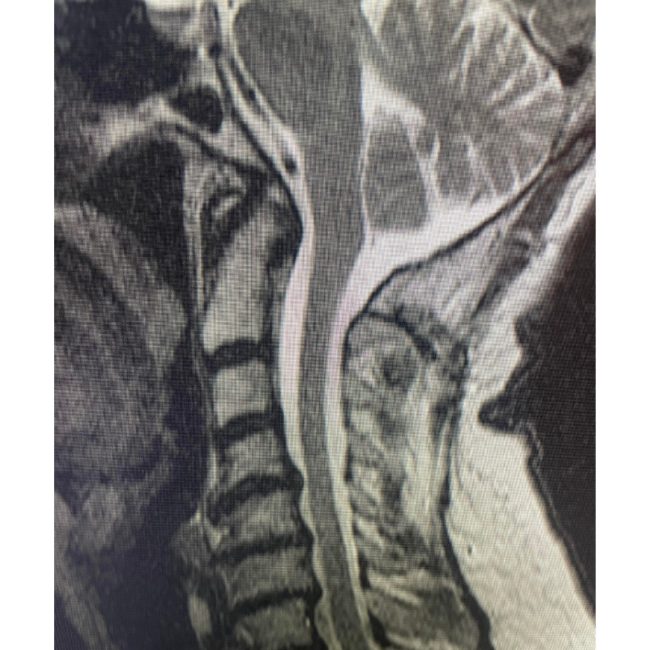

Comprehensive Anterior–Posterior Fusion Restores Alignment and Function for L4–5 Deformity

👉 Spinal deformities / Anterior-posterior (front-back) Spinal Fusion — At Texas NeuroSpine Surgery, our goal is to always find the least invasive approaches for the best surgical outcome. However, some cases require more extensive approaches, as in this case of an L4-5 deformity in a patient with rheumatoid arthritis and years of debilitating low back…